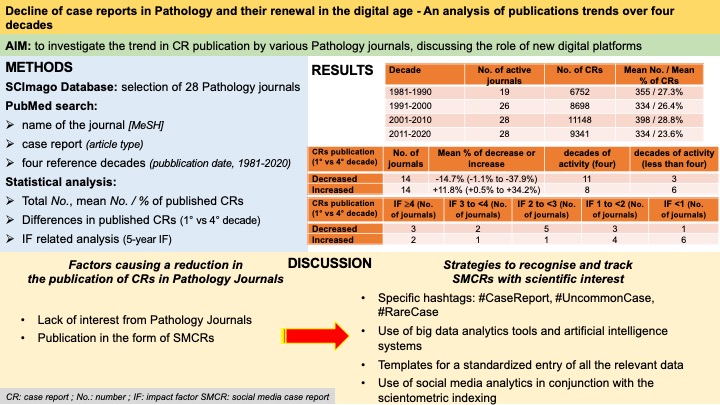

As #pathologists we like writing case reports, but what have been their publication trends in our major Journals over the past 40 years? How we can value the #socialmedia #PathTwitter CRs? To learn more about the topic our latest article on JClinPath_BMJ pubmed.ncbi.nlm.nih.gov/36526332/